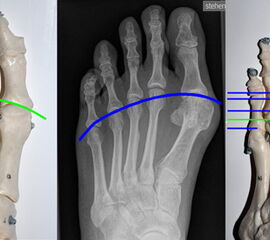

Die Indikationsstellung des geeigneten Operationsverfahrens erfolgt nach dem Schweregrad der Hallux valgus Deformität (Lehmann  DE, 2003). Diese kann anhand verschiedener Winkelparameter graduiert werden, nämlich dem Hallux valgus Winkel, dem Intermetatasale – I – Winkel sowie dem distalen Gelenkflächenwinkel, der häufig auch als PASA-Winkel bezeichnet wird (Abb. 1 – 4). Bedeutsam für die Wahl des geeigneten Vorgehens ist auch die Berücksichtigung der Kongruenzsituation der Gelenkpartner im Großzehengrundgelenk, der durch ein entsprechendes Weichteilrelease Rechung getragen werden muß. Nach der Korrektur soll ein harmonisches Vorfußalignement erreicht werden (Abb.5) (Maestro M, 1995, Ludloff  K,  1918, Pisani G, 1998).

Metatarsaleköpfchenparabel nach Maestro und Pisani

Abbildung 5

• Abbildung 5: Markus Walther